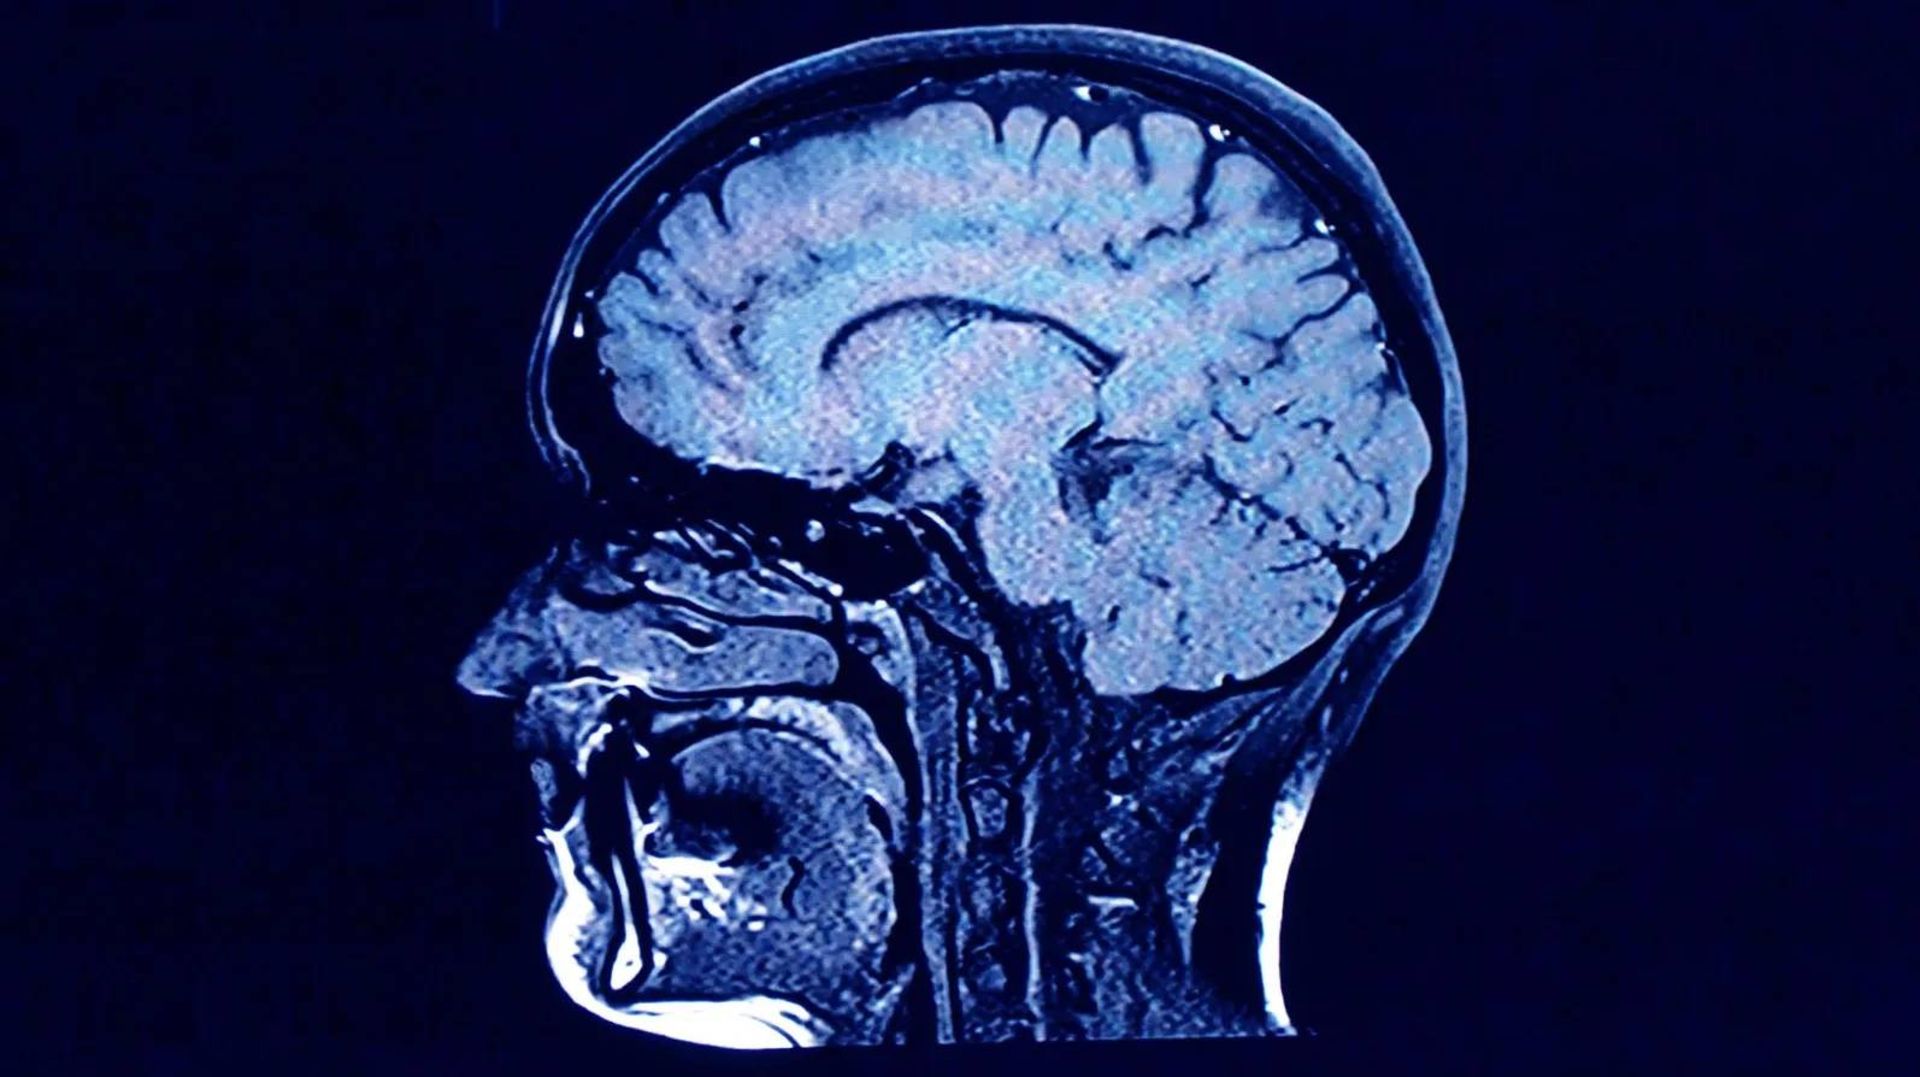

نورون و مغز

آیا ما در بزرگسالی نورون‌های جدید تولید می‌کنیم؟ پالس بمب به یافتن پاسخ این سوال کمک کرده است.

در سال ۲۰۱۳، پژوهشگران از پالس بمب برای بررسی ترن‌آور (جایگزینی سلول‌های قدیمی با جدید) سلول‌های مغزی استفاده کردند. برای سال‌های متمادی، پژوهشگران تصور می‌کردند تعداد نورون‌ها در دوران کودکی ثابت می‌شود. در واقع پژوهش‌های گذشته نشان داده بود در مناطقی مانند قشر مغز این مورد صادق است. بااین‌حال با استفاده از کربن ۱۴ برای تعیین سن نورون‌های هیپوکامپ مشخص شد که ممکن است در بزرگسالی نورون‌های تازه‌ای در هیپوکامپ تولید شود.

عصب‌زایی در بزرگسالی یکی از مهم‌ترین اکتشافات علم عصب‌شناسی در ۲۰ سال گذشته است. درحالی‌که هنوز نادانسته‌های زیادی وجود دارد، این اکتشاف می‌تواند به ایجاد استراتژی‌هایی برای جلوگیری از تخریب نورون‌ یا حتی تولید نورون‌های جدید کمک کند.